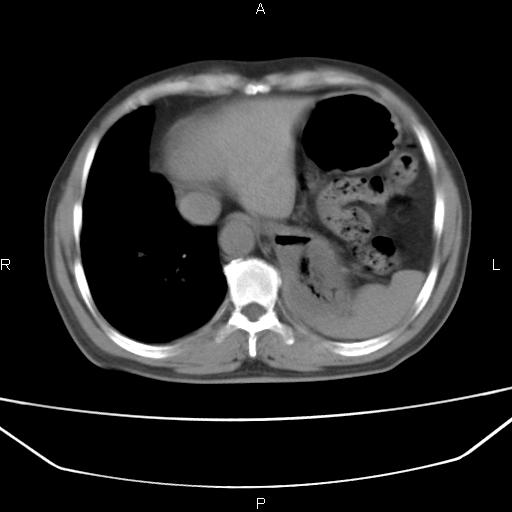

患者,男。50岁。近几日有咳嗽症状,无其他不适,既往病史无,考虑膈疝。请前辈们看看指导指导。

膈膨升,左下肺通气不良,膈肌好像还完整。

考虑左侧膈疝。

左侧膈疝。

符合隔膨升,膈肌较完整。